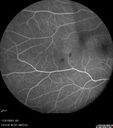

Central Retinal Vein Occlusion - Non-Ischemic - Excellent Outcome17 views57 year old man The right eye has had vision loss for about 3 weeks. He woke up with vision loss.

Medical Hx: HIV . Diabetes Mellitus (since 2014). Thyroid Disease.

Systemic Meds: gemboya. Metformin Hydrochloride. trulicity. losartan. vesepa. Synthroid .

VA OD: sc20/160 OS: sc20/20

TP: OD:14 OS:14

Treated with Avastin

VA 6 weeks later 20/32 – dry one shot.

Missed follow-up after second treatment and came 5 months later with good vision and no macular edemaAug 17, 2025